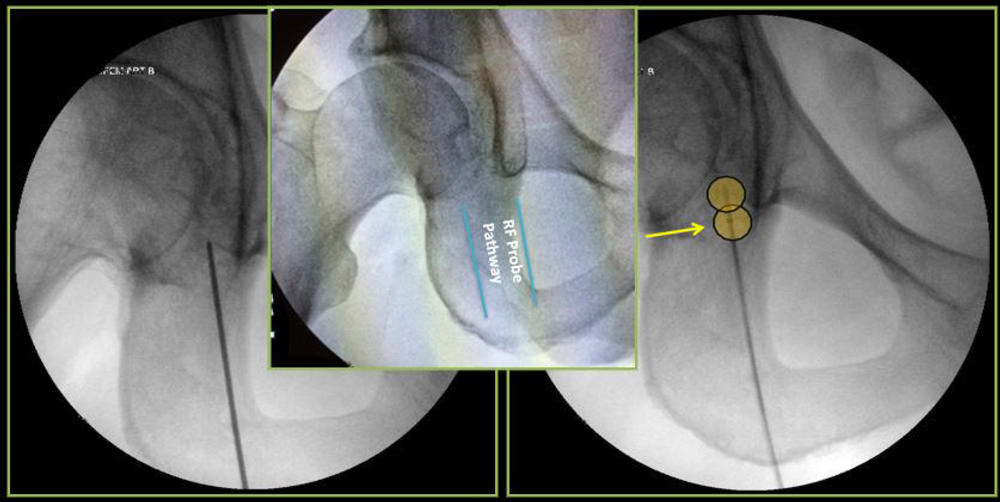

Dr. Gonzalez and colleagues have been studying the application of a novel interventional radiology treatment known as cooled radiofrequency ablation (c-RFA) to achieve pain relief in the setting of advanced degenerative arthritis. The procedure involves the placement of needles where the main sensory nerves exist around the shoulder and hip joints. The nerves are then treated with a low-grade current known as radiofrequency that “stuns” them, slowing the transmission of pain to the brain.

Figure 5. Suprascapular nerve cooled radiofrequency ablation: Target #1

High-res (TIF) version

Figure 6. Suprascapular nerve cooled radiofrequency ablation: Target #2

Figure 7. Axillary nerve cooled radiofrequency ablation: ablation targets.

Figure 8. Axillary nerve cooled radiofrequency ablation: Ablation target #3.

Figure 9. Axillary nerve cooled radiofrequency ablation: Ablation target #4.

Figure 12. Hip-specific cooled radiofrequency ablation technique: There are three ablation targets.

Figure 13. Hip cooled radiofrequency ablation: Obturator nerve ablation.